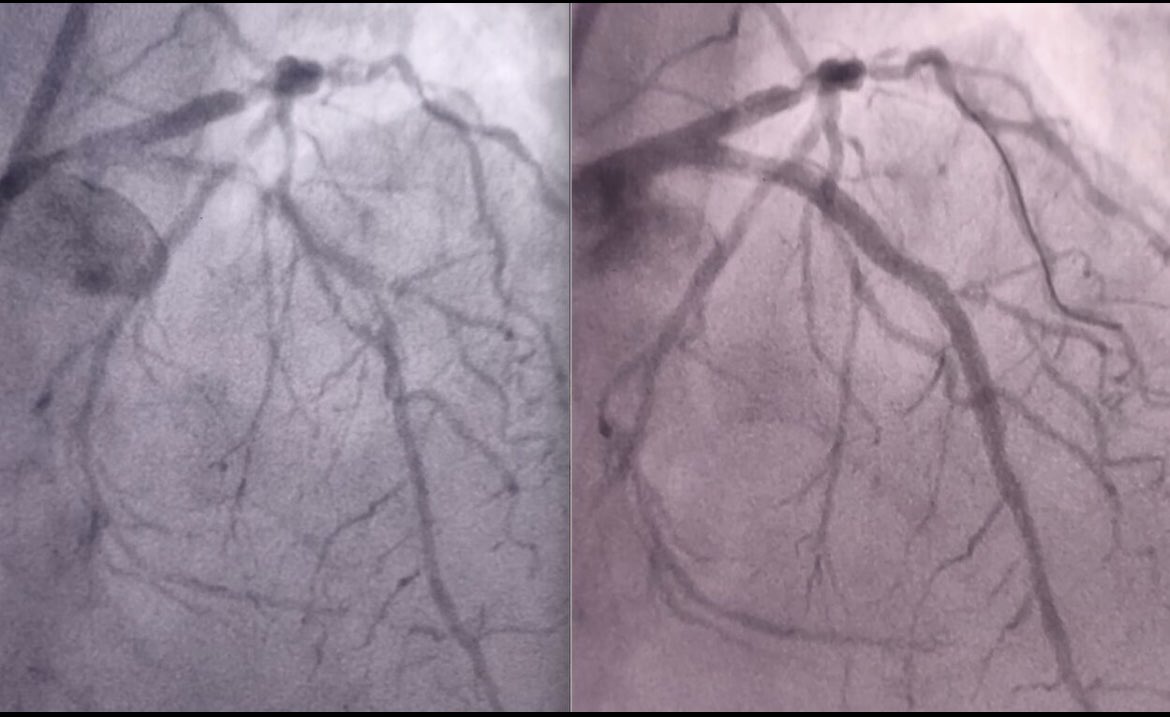

PCI of Severely calcified RCA. Sion Blue over #Turnpike MC. Exchange by Rotawire and rotational atherectomy with #RotaPro system with 1.75 burr. 2 overlap DES. Good result after post-dilatation with 4.0 NC balloon. @AJuradoRoman @hemodin90 @pilarhockey @shci_sec #Trapliner

Hemodin_LaPaz's tweet image. PCI of Severely calcified RCA. Sion Blue over #Turnpike MC. Exchange by Rotawire and rotational atherectomy with #RotaPro system with 1.75 burr. 2 overlap DES. Good result after post-dilatation with 4.0 NC balloon. @AJuradoRoman @hemodin90 @pilarhockey @shci_sec #Trapliner